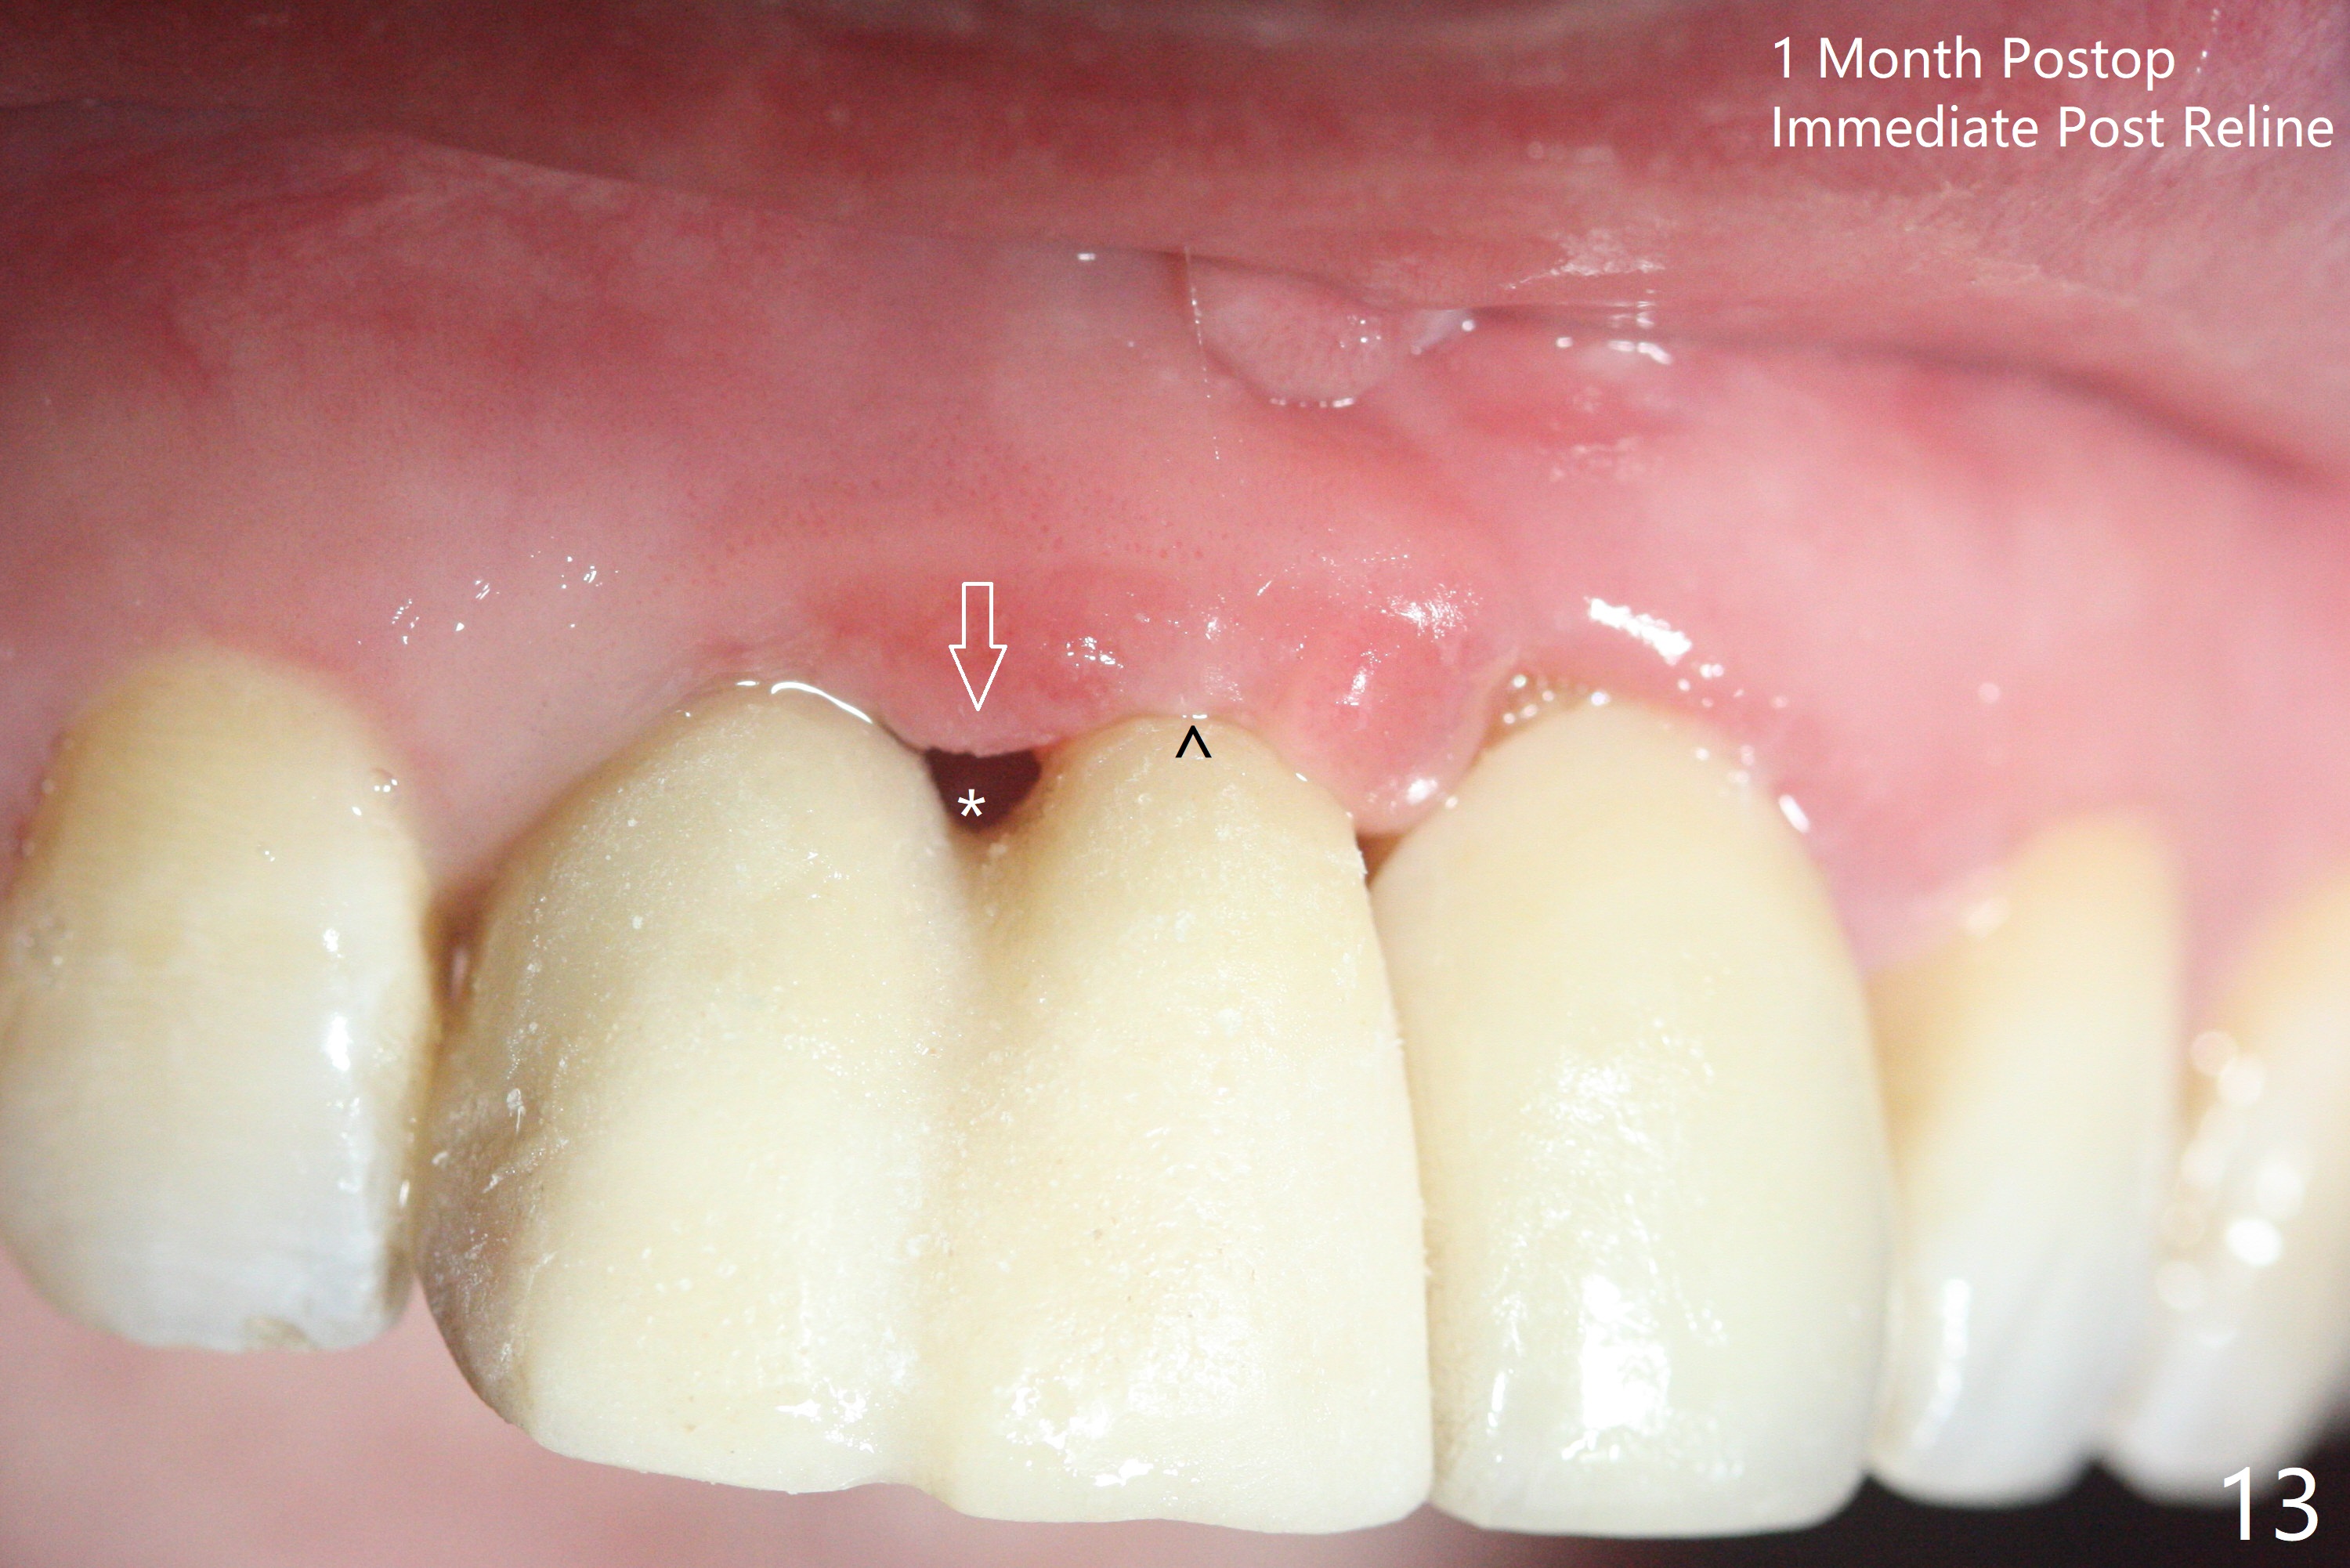

拆除部分桥发现:中,侧切牙牙龈红肿(图一),不利于切口和伤口愈合。不过还是在中切牙区切开,牙龈相当厚,有利于今后牙龈形成凹陷和乳头。坏消息是近远中距离太短,不利于植牙以及今后局部卫生维护,所以决定只在侧切牙种植(图二,三),完成钻洞后,颊侧根尖穿孔植骨,然后植入植体,即刻放置修复基台(图四 (*:牙龈乳头)),暴露基台牙龈缘,制作临时悬臂桥 (图五),两个中切牙牙冠长度差不多,插入临时桥时颊侧牙龈乳头基本形成(图六:*),缝合前颊侧,腭侧牙龈瓣下放置粘性骨块(图七,八:* )和PRF膜(图七:^)。最后使用牙周敷料。但愿术后牙龈炎症消失,形成良好牙龈乳头和pontic concavity。 其实由于口腔卫生习惯,术后十七天颊侧牙龈仍红肿(图九),而腭侧正常。如果口腔卫生改善而红肿依然存在,让实验室制作临时桥。术后一个月颊侧牙龈红肿好些(图十),好像骨粉丢失少许,可能与水枪使用有关。右上1牙冠显得太短(*)。也太肥大,因为右上1切缘太颊侧,与左上1对比(图十一:*)。由于颊侧牙龈(图十二:B)术中推向颊侧,与腭侧(P)牙龈之间放置大量粘性骨粉,术后一个月骨粉(<)形成牙龈,形成凹陷。颊侧萎缩不再明显了。右上1牙冠颈部多加些树脂,牙齿就显得长的多(图十三:箭头)。与侧切牙之间颈部故意留下间隙(*),让牙龈入位(空箭头),形成龈乳头。当右上1临时牙冠切缘(图十四:*)移到腭侧,外形改观不少。下次改善侧切牙唇侧。术后两个月三个星期牙龈红肿好像减轻,牙龈没有进入切牙间隙,干脆用树脂关闭(图十五:> <)。下次减少侧切牙切缘(^),适当增加中切牙长度(上提牙龈)。术后3.5个月植体好像整合,基台完全就位(图十六)。术后3.5个月Pontic凹陷形成,但是1,2之间龈乳头始终无法形成(图十七)。以后类似病例应该多种植一个。此例草率取模,可能需要临时粘固,观察植体近中颊侧所谓瘘道,必要刮治。由于比色不佳,需要实验室颜色更改,病人强化卫生,术后七个月,永久性牙冠粘固前,局部牙龈健康(图十八)。